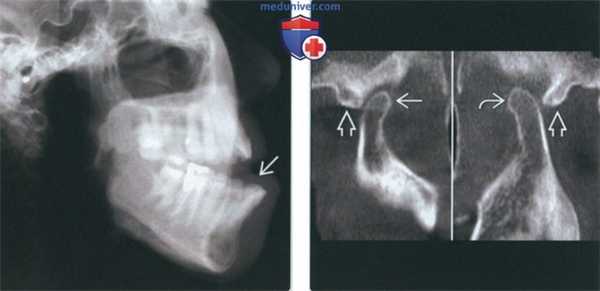

(Слева) На панорамной рентгенограмме у пациента с двухлоронним передним вывихом визуализируется правый мыщелок, смещенный кпереди и кверху относительно сулавного возвышения. Обратите внимание на явный передний открытый прикус, в то время как моляры находятся в окклюзии.

(Справа) На панорамной рентгенограмме у этого же пациента определяются аналогичные изменения слева. Открытый прикус обусловлен неправильным передним положением мыщелка, контакт задних зубов - его верхним положением.

(Слева) На рентгенограмме в боковой проекции у этого же пациента определяется прогнатическое положение нижней челюсти и открытый передний прикус вследлвие передне-верхнего смещения мыщелков нижней челюсти.

(Справа) На сагиттальной КЛКТ правого и левого мыщелков у этого же пациента определяется, что мыщелки расположены спереди и сверху относительно сулавных возвышений. Обратите внимание, что мыщелки имеют нормальную форму, а кортикальная плалинка не изменена.